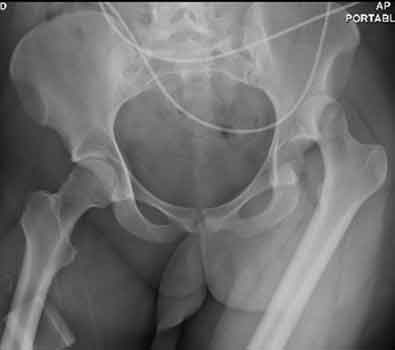

22) Name the abnormality shown in the image below.

23) What abnormalities of the pelvis can be observed in the image below?

24) Based on your findings, name the condition shown in the image above.